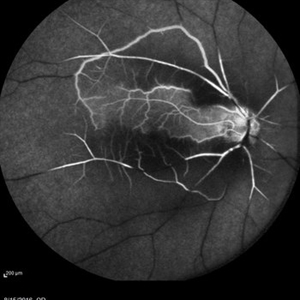

Fluorescein angiography of a 68-year-old woman with decreased vision for past few months following viral illness.